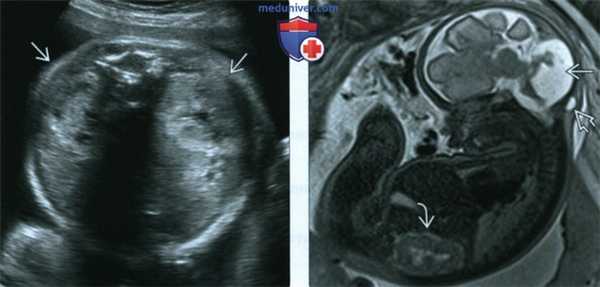

(Слева) Тот же плод. УЗИ брюшной полости. Обе почки увеличены и гипер-эхогенны, что позволяет заподозрить СЖ с поражением почек.

(Справа) МРТ в сагиттальной плоскости. Отмечаются аномалии структур ЗЧЯ, затылочное энцефалоцеле и увеличение почки. МРТ плода позволяет прицельно исследовать определенную часть тела (в данном случае - головной мозг), однако нередко возможно получить достаточный объем диагностических сведений на основании обычных «поисковых» методов.